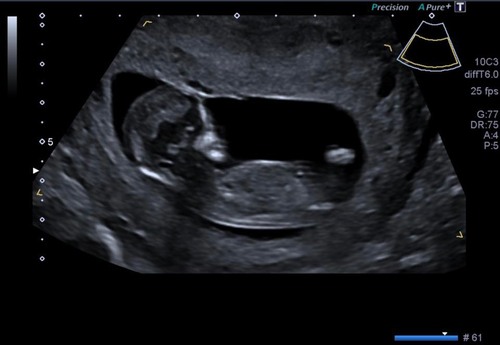

We hebben deze week onze geslachtsecho, super spannend! Deze echo was gemaakt met 13+2, wil iemand nog een gokje wagen? :)

We hebben deze week onze geslachtsecho, super spannend! Deze echo was gemaa ...

Meisje

Goed geraden hier, we krijgen een meisje! 💖🥰